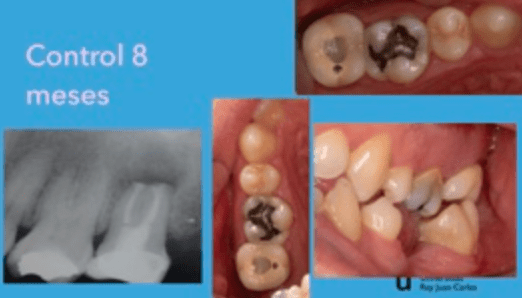

Pulpotomía biodentine + reco preendio